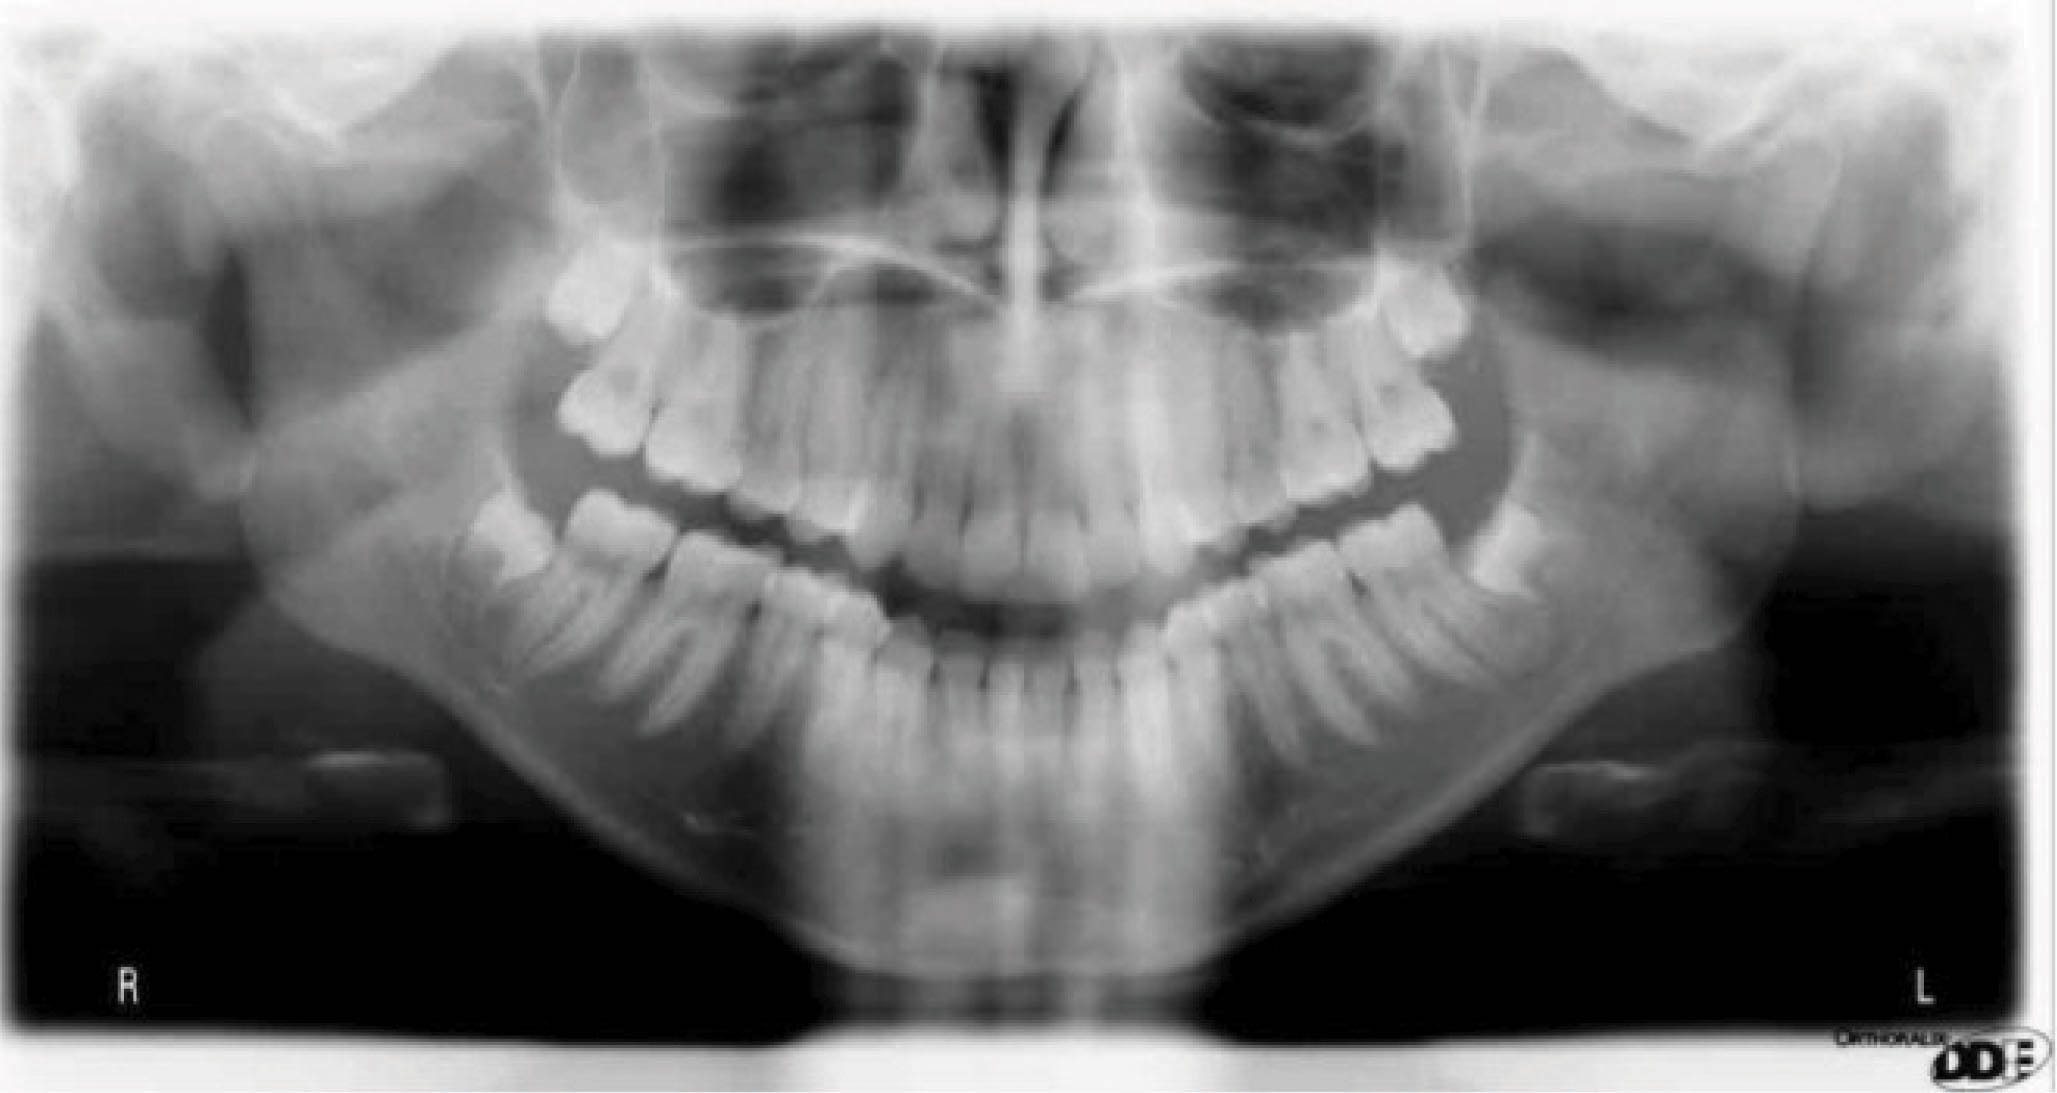

نتایج درمان (شکل 20-6) و عکس طراحی کامپیوتری (شکل 21-6) خیلی به هم شبیه شدند. عکس OPG هم طبیعی است.

شکلهای 26-6 و 27-6 نتایج درمان در قیاس با طراحی کامپیوتری را نشان میدهند. عکس OPG هم طبیعی است (شکل 28-6).

با سوپرایمپوز کردن لترال سفالومتری در شکل 35-6 شاهد سه درجه پروترود شدن انسیزورهای پایین هستیم. ارتفاع عمودی ثابت ماند و کنترل خوبی در حفظ زاویه پلن مندیبل داشتهایم. رادیوگرافی OPG پایان کار (شکل 36-6) طبیعی است. مدت نگهدارنده ۳۰ ماه بود و همه چیز خوب حفظ شده است (شکل 37-6).